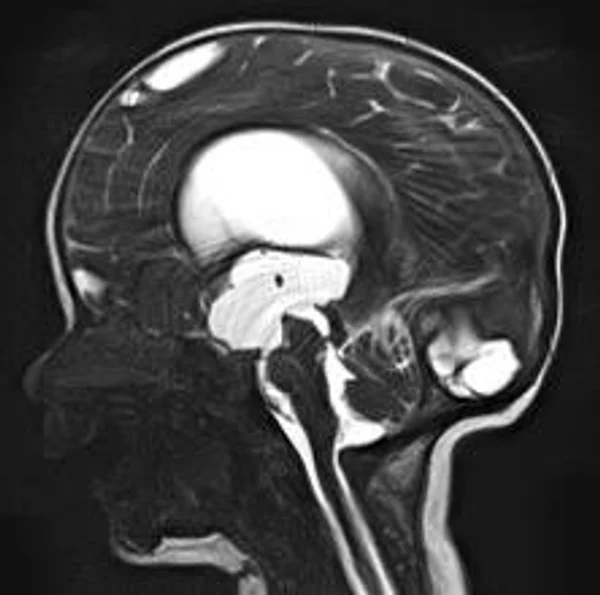

Гидроцефалия

Основной причиной гидроцефалии является окклюзия ликворных путей, встречающаяся у новорожденных детей в 60-70% случаев, к 3 годам частота окклюзионной гидроцефалии достигает 90%. Поэтому основной задачей лечения гидроцефалии являются устранение окклюзии ликворных путей, восстановление циркуляции ликвора и нормализация внутричерепного давления. В настоящее время эти задачи успешно позволяют решить эндоскопические методы хирургического лечения гидроцефалии. Эндоскопические операции проводятся нами во всех возрастных группах, включая недоношенных новорожденных детей, при разных локализациях и количествах окклюзий. При этом если эндоскопическая перфорация дна III желудочка (син.: эндоскопическая III-вентрикулостомия) малоэффективна у детей до 2-3-х летнего возраста, то новые методы эндоскопических операций, направленные на реканализацию естественных путей оттока ликвора с имплантацией стента (например эндоскопическая акведуктопластика, стентирование водопровода мозга) позволяют избежать имплантации шунтирующих систем у большинства пациентов с окклюзионными формами гидроцефалии. С целью снижение объема секреции ликвора и увеличения эффективности эндоскопических опеарций в некоторых случаях в комплексе с другими эндоскопическими операциями проводится эндоскопическая плексусэктомия. Операция заключается в коагуляции сосудистых сплетений боковых желудочков с последующим удалением их гломусных частей. Эндоскопические операции также проводятся при дисфункции ранее установленных шунтирующих систем у пациентов с окклюзионной гидроцефалией, что часто избавляет пациента от «шунт зависимости» и создает условия для удаления шунта. Имплантация ветрикулоперитонеальных, вентрикулоатриальных и др. шунтирующих систем нами применяется при сообщающейся форме гидроцефалии. У пациентов с окклюзионными формами гидроцефалии шунтирующие операции проводятся только при неэффективности ранее проведенных эндоскопических операций.